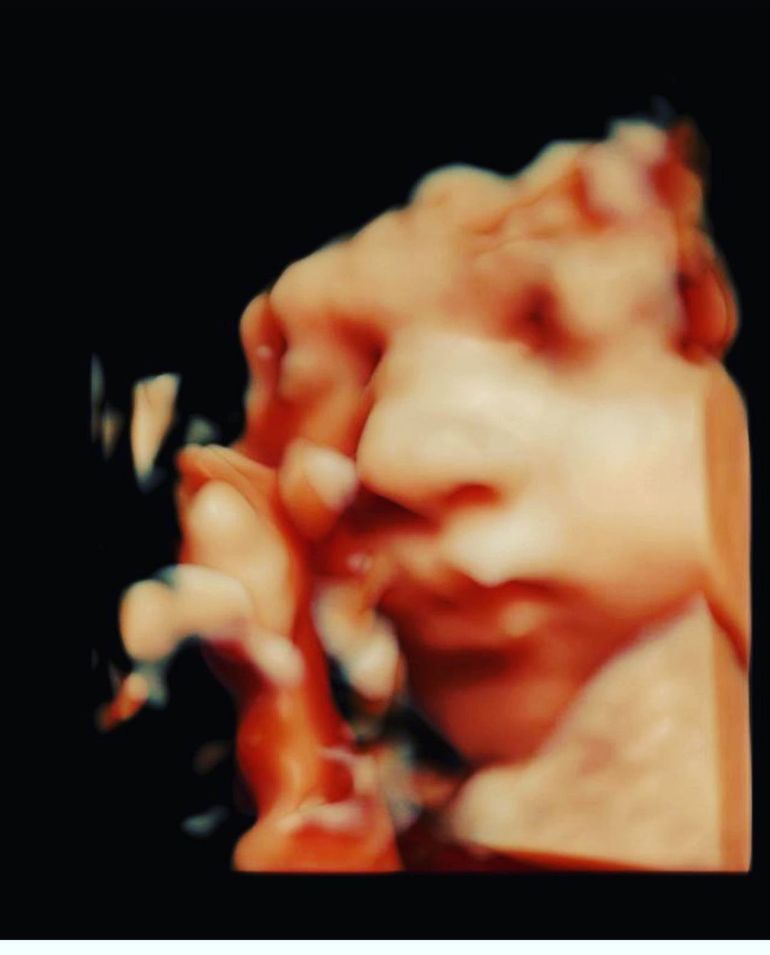

Laurențiu Reghecampf a postat prima imagine cu chipul celui de-al treilea fiu al său! Ce nume a ales pentru băiețel?

Așadar, în postarea sa, Laurențiu Reghecampf a dezvăluit că pe noul moștenitor îl va chema Liam, potrivit declarației sale din mediul online.

”Astăzi dimineață s-a născut Liam, frățiorul vostru ! Va iubește tata❤️”, a scris Laurențiu Reghecampf în dreptul unei fotografii cu cei doi băieți ai lui.